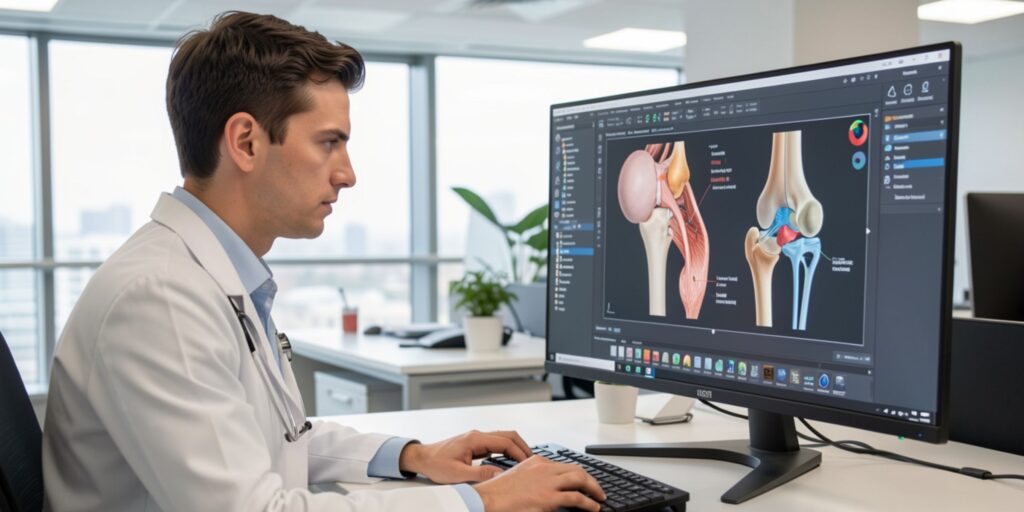

Tumour reconstruction and joint preservation focus on restoring stability and movement after surgical removal of bone or soft tissue tumours. When a tumour affects areas near a joint, careful surgical planning is essential to remove diseased tissue while maintaining as much natural joint structure as possible. At the practice of Dr. Narendra Singh Butola in Dehradun, advanced reconstructive techniques are used to balance oncological safety with long-term mobility and functional independence.

Each tumour location and extent requires an individualised approach. Reconstruction may involve bone grafting, specialised implants, or biological techniques depending on the case. Careful post-operative rehabilitation planning ensures gradual return to daily activities with improved confidence and function.